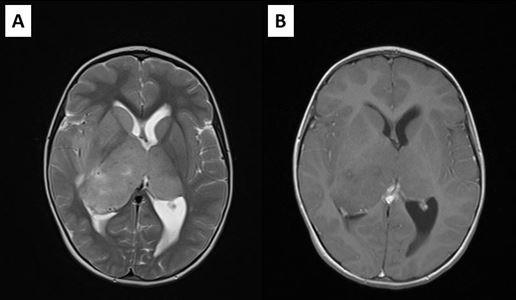

We present a case of a 5-year-old girl admitted with signs of raised Intracranial Pressure (headache, vomiting and lethargy) (ICP) and left sided hemiparesis that lasted for two weeks. Systemic examination was normal and neurological examination revealed upward gaze palsy, mild left sided hemiparesis, and chronic papilledema with 2.5D on the left, and 3.5D on the right eye. Brain CT scan showed large isodense mass involving bithalamic region with right sided predominance and ventricular enlargement. There was no contrast enhancement (Figure 1). Brain MRI showed huge bithalamic lesion, with some right sided predominance. It was uniformly isointense on T1 weighted and, hyperintense on T2 and FLAIR weighted images, with no contrast enhancement. Lateral ventricles were enlarged (Figure 2). After VP shunt placement and corticosteroid therapy symptoms resolved. In the second surgery patient was operated through the right, nondominant parietal lobulus since tumor mass was larger in the right thalamus, filling the body of the right lateral ventricle with significant lateral and posterior extension. During the operation body of the right ventricle was entered, and intraventricular tumor mass was removed. Tumor was without clear border to right thalamus. Most of the right sided mass was removed. Postoperative course went uneventful.

Postoperative MRI showed residual tumor in the left thalamic region, and radiotherapy was performed, followed by chemotherapy. Residual tumor regression was confirmed with MRI, and the patient was stable almost for 2 years. She was monitored with MRI every 3 months (Figure 3). However, twenty-one months after surgery and two months after previous brain MRI which showed no signs of tumor regrowth, child was referred to our department with acute consciousness deterioration, drowsy, adynamic with Glasgow coma score of 10 points. Brain CT showed bleeding in the region of the corpus callosum, and MRI, confirmed bleeding within the genum of corpus callosum and symmetrical extension into the white matter of both frontal lobes. On the post contrast tomograms tumor component could not be identified (Figure 4). The patient had low platelet number, so impaired coagulation was suspected as the cause of bleeding. MSCT angiography was normal. Hematoma was evacuated and biopsy samples were taken. The child recovered well after operation. Pathohistological examination revealed that the cause of bleeding was high grade glial tumor. This time the definite diagnosis was Glioblastoma.